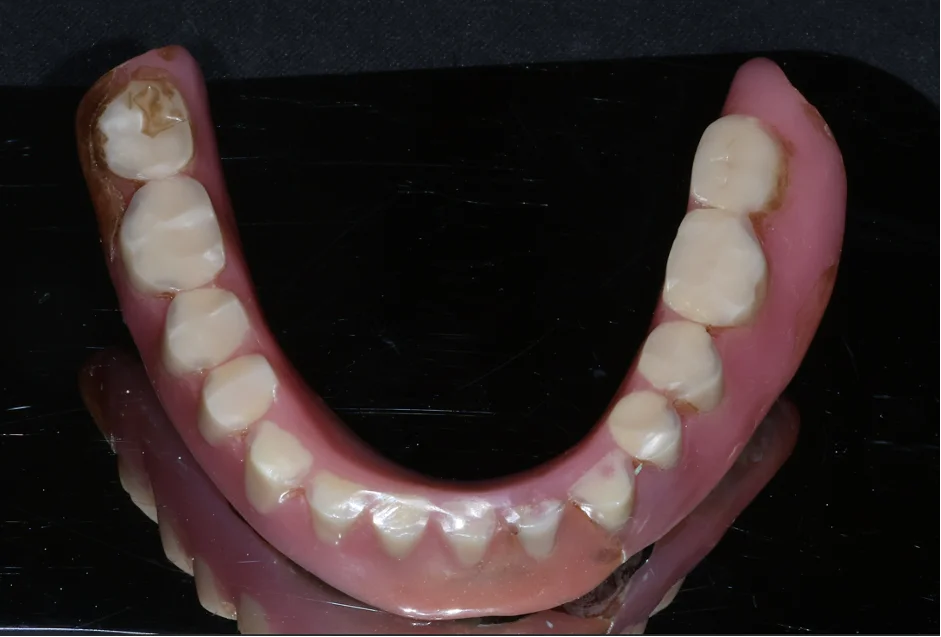

[📸 치료 전 실제 환자 분의 마모된 틀니] (촬영일: 2024년 6월)